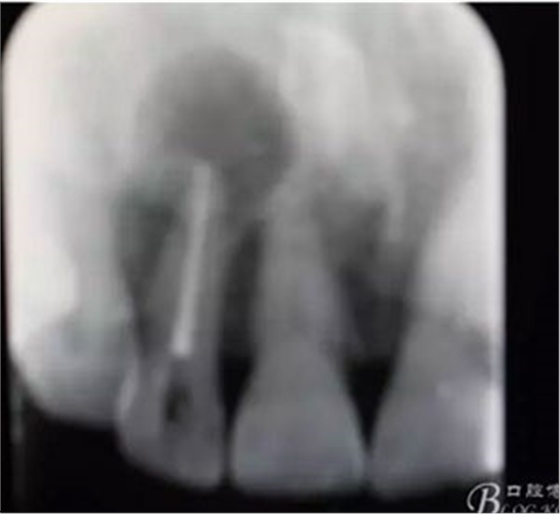

圖2. 12牙齒在我院進(jìn)行熱牙膠根管充填+樹脂充填。

圖21.術(shù)后的x根尖片影像情況。12根尖區(qū)MTA充填完好。